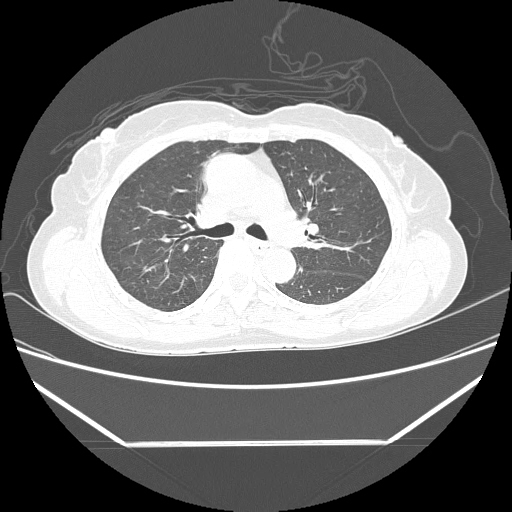

Radiological images:

HRCT is also done on 13/11/15